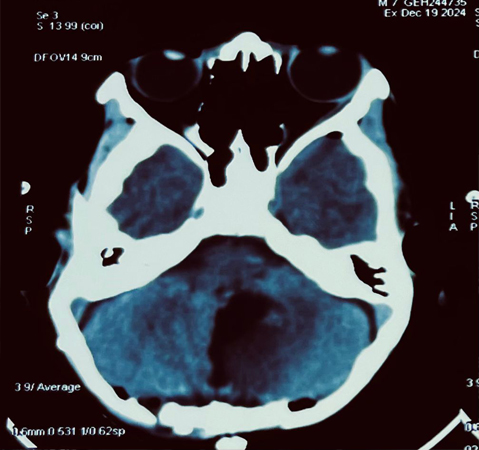

In a groundbreaking surgical feat, the team of expert neurosurgeons at Graphic Era Hospital successfully operated on a 7-year-old child with a large and critically located posterior fossa medulloblastoma. The child, who was admitted in a moribund and lethargic state, underwent a high-precision microsurgical procedure to remove the tumor, which was situated in close proximity to the brainstem.

The surgical team, utilized cutting-edge techniques to safely and successfully resect the tumor. The child has made an excellent recovery and discharged with no new neurological decits. This remarkable achievement marks a rst in Pediatric Brain Tumour Surgery; for Graphic Era Hospital; and underscores the institution's commitment to delivering world-class medical care. The child's family has expressed gratitude to the medical team, hailing the surgery as a "miracle."